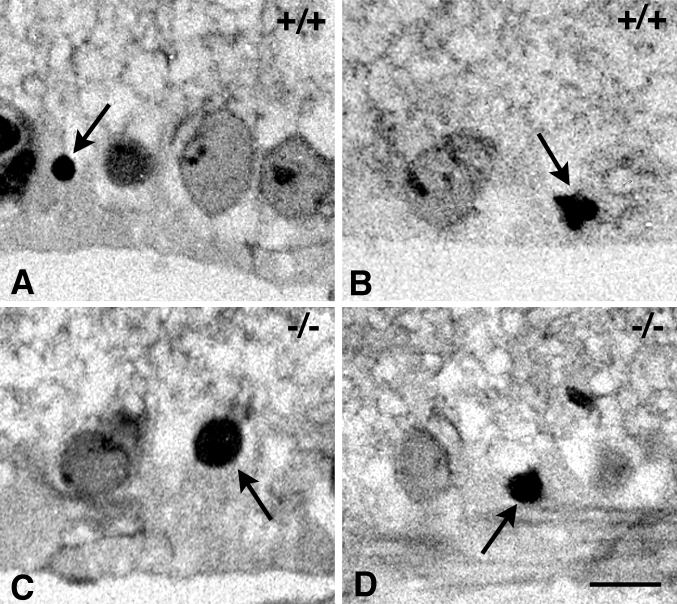

Figure 5. Histologic evaluation of the ganglion cell layer in NMDA treated p53 mutant mice

Cell death in p53 wild-type and p53-null mice is associated with the formation of pyknotic nuclei. Micrographs of toluidine blue-stained retinal sections taken 2 days after injection of 160 nmol of NMDA. A, B: Close-up of the ganglion cell layer of wild-type mice showing both normal appearing and pyknotic nuclei (arrows). C, D: Close-up of the ganglion cell layer of p53-null mice showing similar pyknotic nuclei. Based on morphological criteria, these results suggest that an apoptotic-like mechanism is active in both groups of mice. Size bar represents 7 μm.